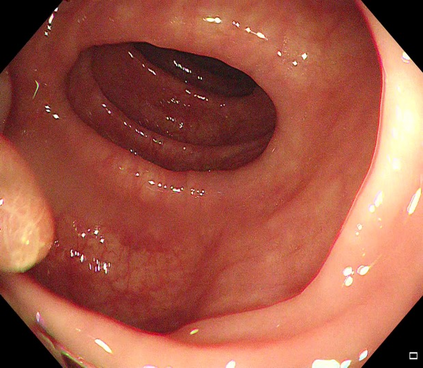

Polyps are early cancer indicators, so assessing occurrences of polyps and their removal is critical. They are observed through a colonoscopy screening procedure that generates a stream of video frames. Segmenting polyps in their natural video screening procedure has several challenges, such as the co-existence of imaging artefacts, motion blur, and floating debris. Most existing polyp segmentation algorithms are developed on curated still image datasets that do not represent real-world colonoscopy. Their performance often degrades on video data. We propose a video polyp segmentation method that performs self-supervised learning as an auxiliary task and a spatial-temporal self-attention mechanism for improved representation learning. Our end-to-end configuration and joint optimisation of losses enable the network to learn more discriminative contextual features in videos. Our experimental results demonstrate an improvement with respect to several state-of-the-art (SOTA) methods. Our ablation study also confirms that the choice of the proposed joint end-to-end training improves network accuracy by over 3% and nearly 10% on both the Dice similarity coefficient and intersection-over-union compared to the recently proposed method PNS+ and Polyp-PVT, respectively. Results on previously unseen video data indicate that the proposed method generalises.